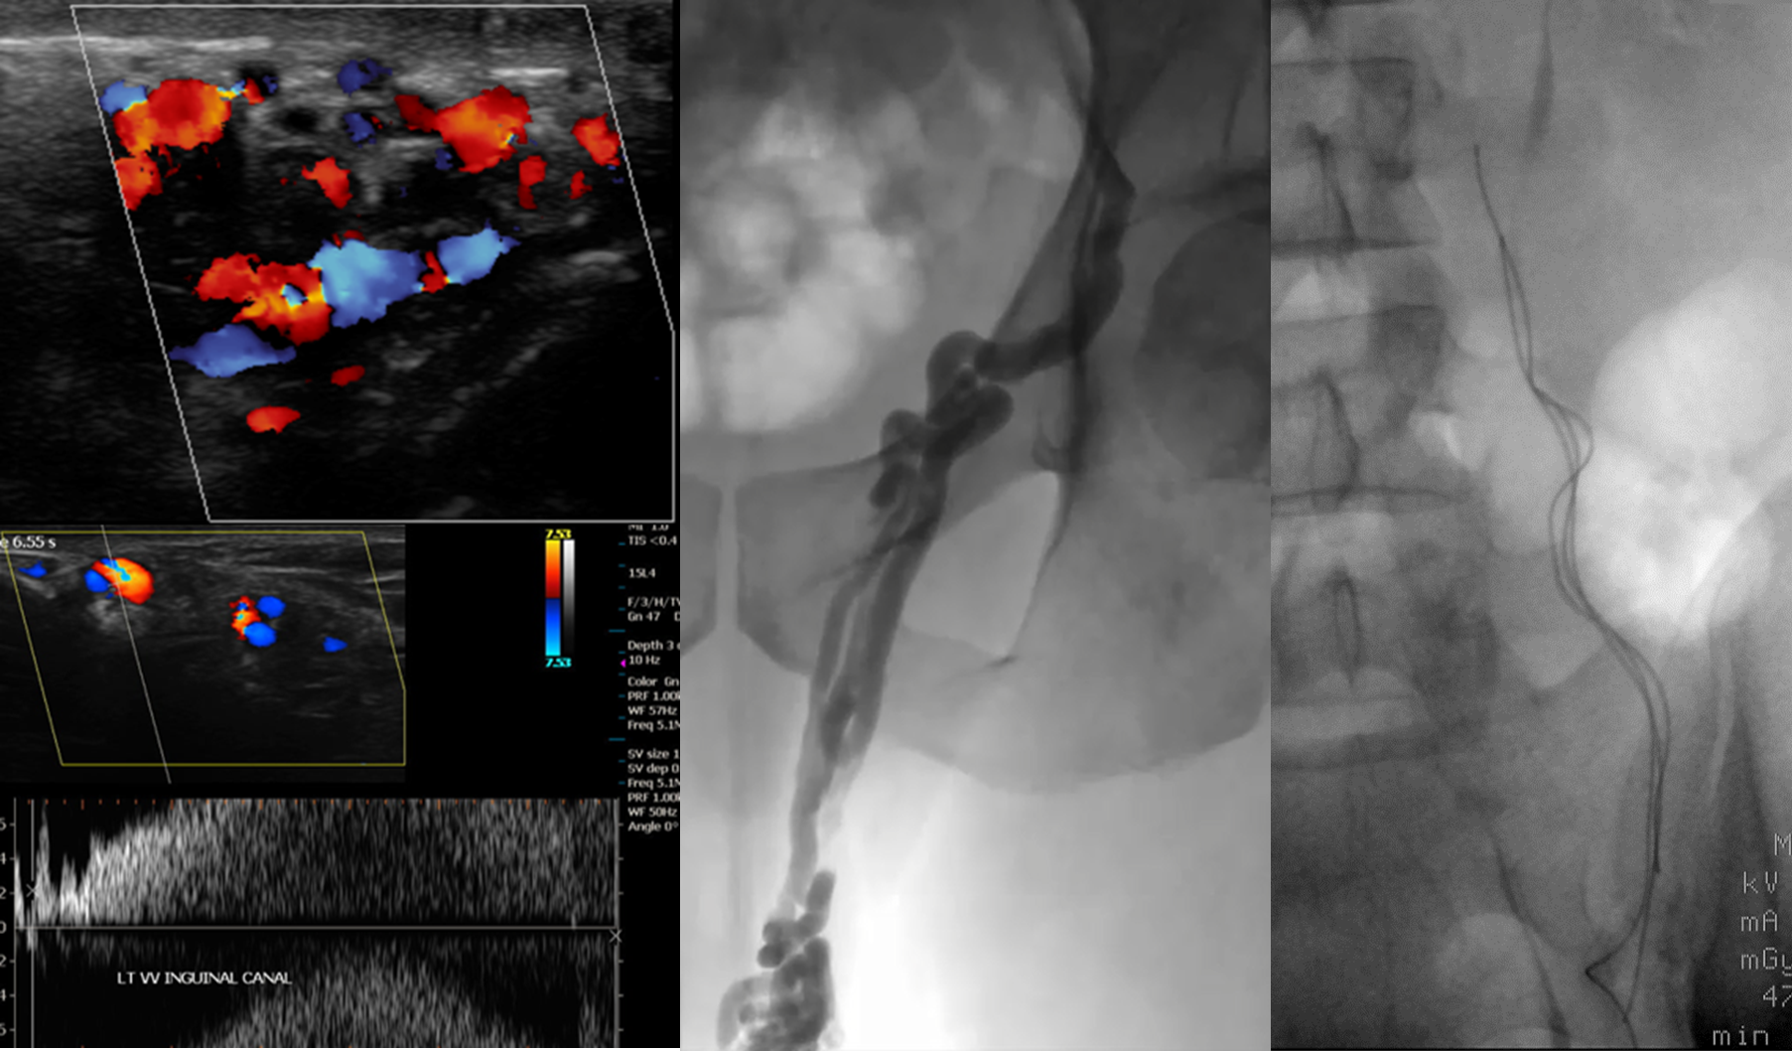

from radiopaedia.org

Abdomen Xray shows endovascular coils used to treat varicoceles in Coil Embolization Varicocele Web coils are commonly used embolic for varicocele, and both detachable and pushable coils can be used for. Web varicocele embolization is a minimally invasive method of treating varicoceles by embolizing the testicular. Web varicocele embolization, another procedure to treat varicocele, blocks the vein around the spermatic cord to prevent blood flow. Web coils are the most commonly used embolic. Coil Embolization Varicocele.

An Xray showing embolization coils occluding the testicular vein Coil Embolization Varicocele Web there are several options for the treatment of varicocele, including surgical repair either by open or. Web varicocele embolization, another procedure to treat varicocele, blocks the vein around the spermatic cord to prevent blood flow. Web varicocele embolization is a minimally invasive method of treating varicoceles by embolizing the testicular. Web coils are commonly used embolic for varicocele, and. Coil Embolization Varicocele.